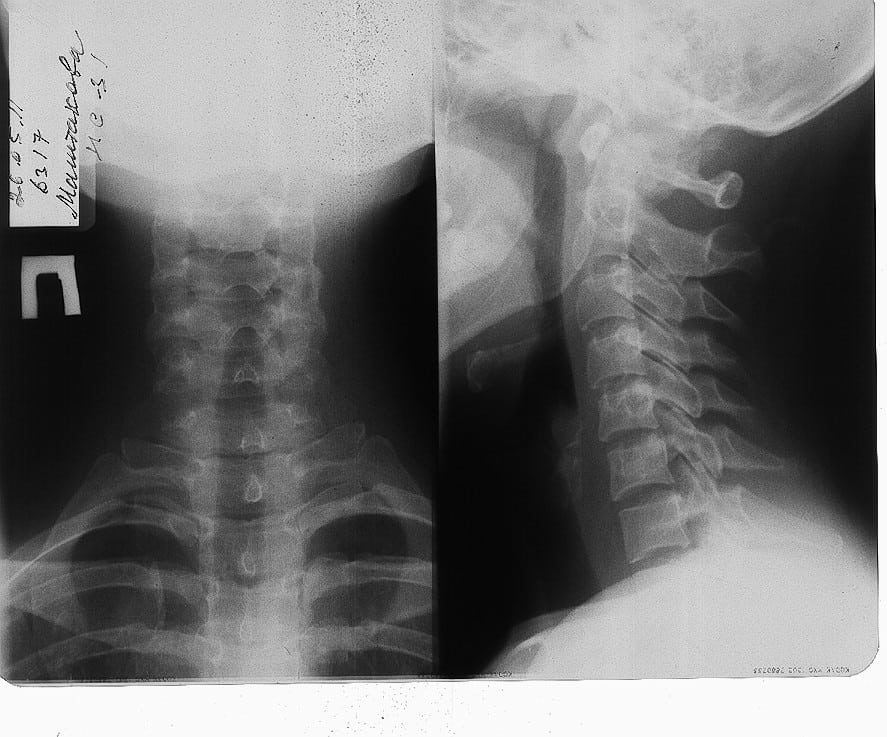

К вертебрологу или неврологу пациенты с шейным остеохондрозом и болью в горле часто приходят с направлением от отоларинголога. Именно к этому врачу обращаются при проблемах с глотанием или подозрении на развитие респираторных патологий. Отоларинголог, а иногда и терапевт, обязательно должен исключить профильные заболевания после проведения необходимых исследований. Опытный врач заподозрит остеохондроз шейной или грудной локализации при внешнем осмотре, после выслушивания жалоб, изучения анамнеза. Настораживающим фактором становится описание пациентом, как болит горло, с перечислением признаков, возникающих при шейном остеохондрозе. Это головокружения, скачки артериального давления, тугоподвижность шеи. Для подтверждения начального диагноза проводятся инструментальные исследования:

- рентгенография;

- МРТ или КТ;

- ангиография.

Для исключения бактериального или вирусного поражения дыхательных путей биологический образец исследуется на наличие патогенных микроорганизмов. Если у пациента не обнаружены инфекции, новообразования, присутствие инородного тела или диафрагмальная грыжа, то он направляется к вертебрологу. Диагноз подтверждается рентгенологическими изображениями, на которых хорошо визуализированы истончившиеся диски, сместившиеся позвонки. А на снимках МРТ отчетливо просматриваются сформировавшиеся межпозвоночные грыжи. Во время диагностирования нередко требуется помощь врачей узкой специализации — эндокринолога, гастроэнтеролога, ревматолога, психотерапевта.